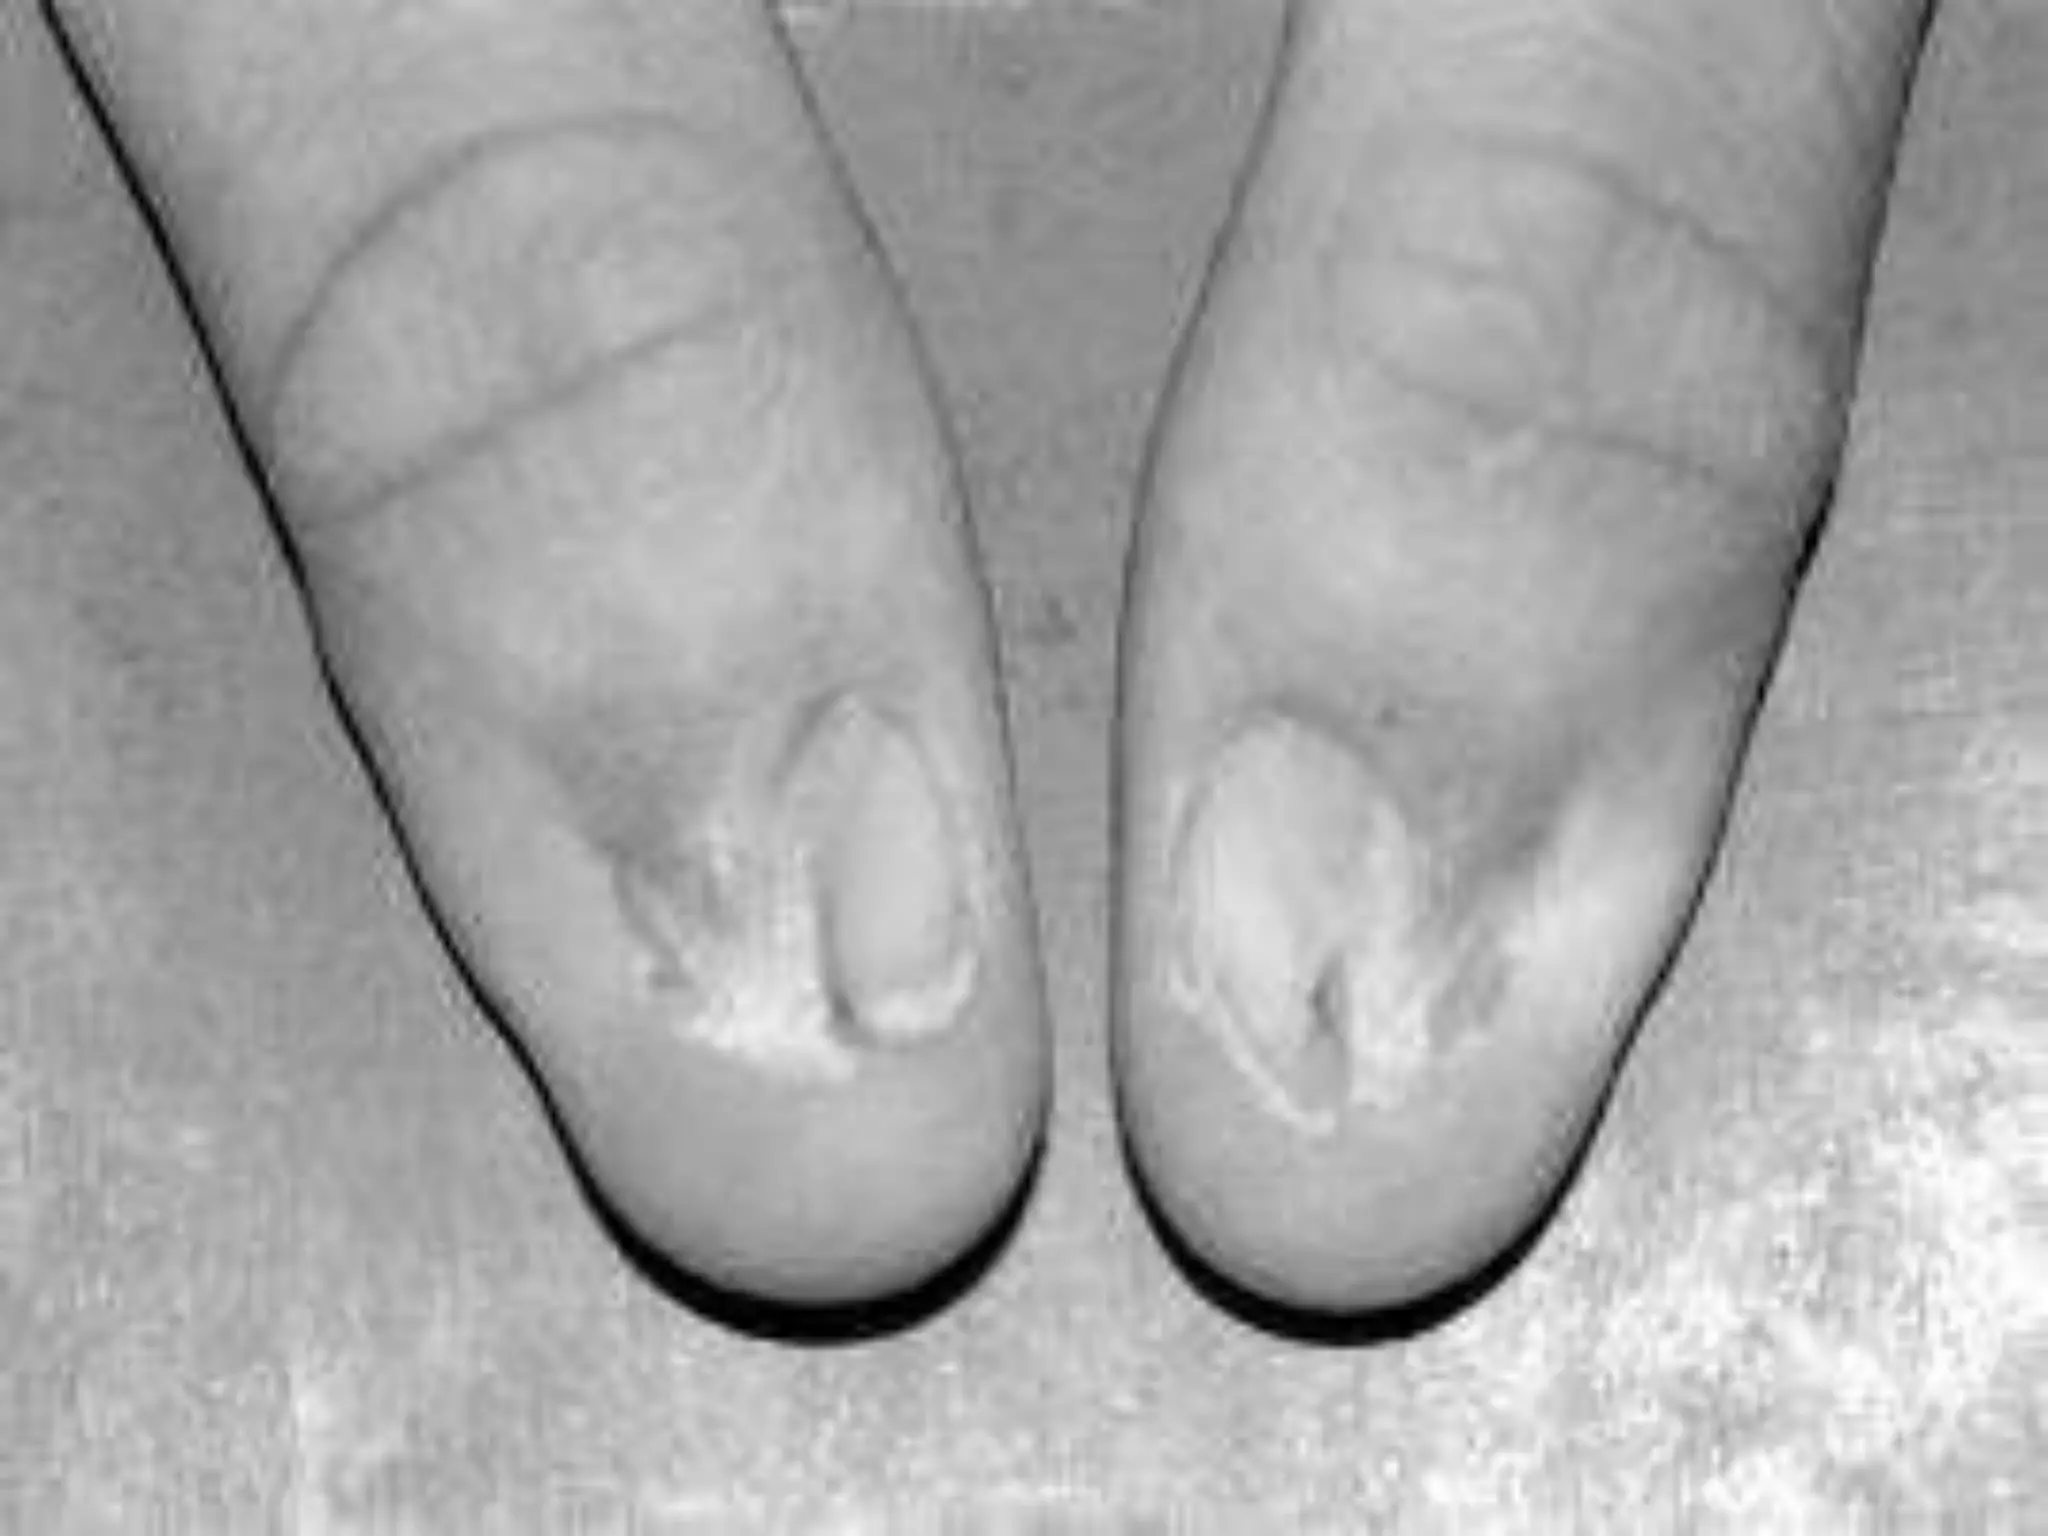

Crippled hand

(Fingers/toes have multiple

enchondromata characteristic

of disease)

Mafucci’s syndrome(rare)

Dyschondroplasia /Enchondromatosis/Ollier’s disease Rarebut easily recognised Defective transformation of physeal cartilage into bone unilateral short limb Valgus/varus deformity knee/ankle Shortened ulna Bowing radius Crippled hand (Fingers/toes have multiple enchondromata characteristic of disease)

• 30.

Mafucci’s syndrome(rare) characterised bymultiple enchondromas. Soft tissue haemangiomas (skin/viscera). Malignant changes in soft tissue and bone lesions.